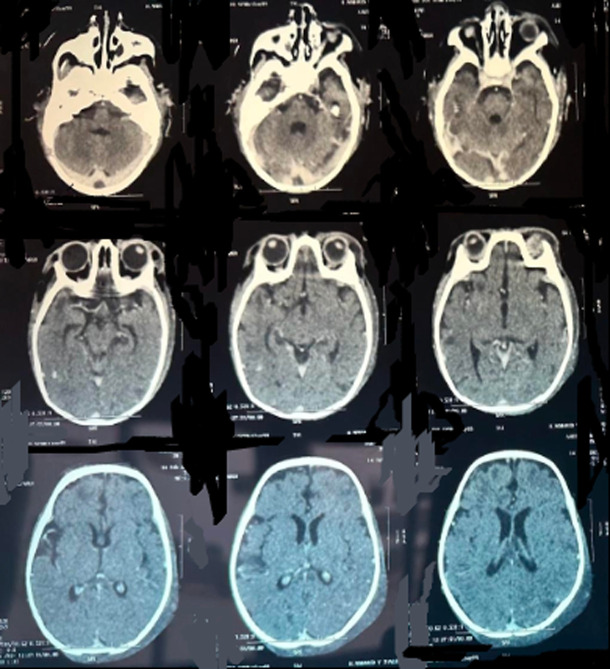

我们正在处理一个女婴病例,她有脑静脉血栓,显示继发性免疫缺陷,由于人类免疫缺陷病毒感染。在用低分子肝素(LMWH)进行抗凝治疗后,发现她患有严重的血小板减少症,这表明血小板减少症是由肝素的自身免疫来源引起的。在发展中国家,确诊手段并不总是可用,因此很难确定严重血小板减少症是由于艾滋病毒感染、败血症还是肝素所致。因此,治疗决定是困难的,因为停止抗凝可能导致脑血栓扩展。

We are dealing with a female infant case who had a cerebral venous thrombosis, revealing a secondary immunodeficiency, owing to a human immunodeficiency virus infection. After anticoagulant treatment with low-molecular-weight heparin (LMWH), it came to light that she had a severe thrombocytopenia, suggesting a thrombocytopenia induced by an auto-immune origin of heparin. Within a developing country in which means of confirmation are not always available, it was difficult to identify whether severe thrombocytopenia was owing to HIV infection, sepsis, or heparin. The therapeutic decision was therefore difficult, because stopping anticoagulation can lead to a cerebral thrombosis extension.